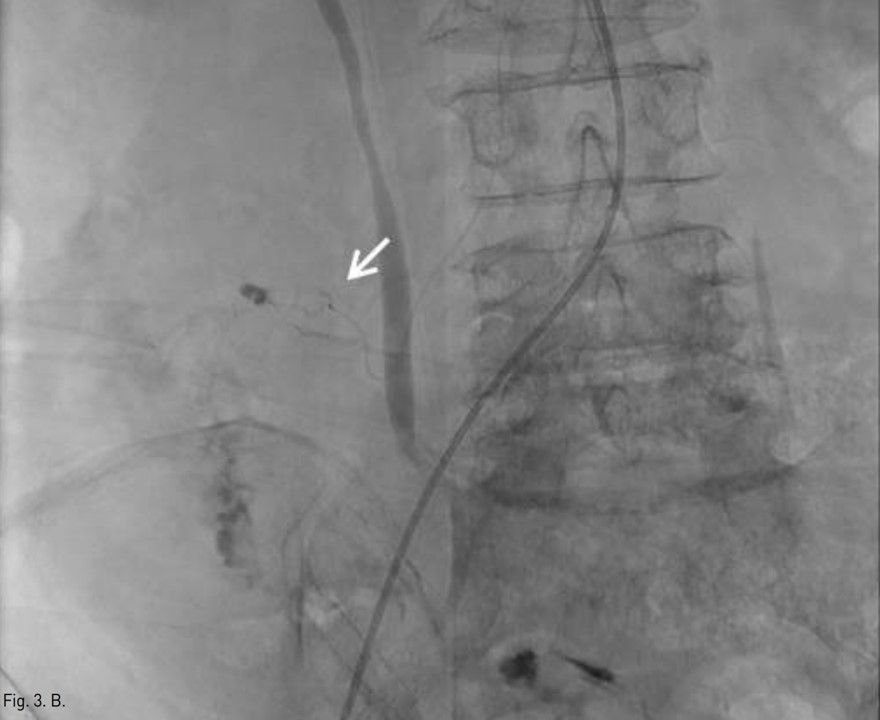

Fig. 2.

Fig. 2. Superior mesenteric angiogram demonstrates multiple pseudoaneurysms with extravasation of contrast media at distal branches of ileocolic (arrows) and right colic (arrowhead) arteries.